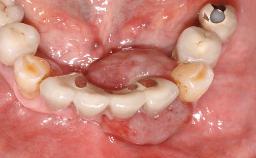

Surgical treatment of a 68-year-old female patient with a distal extension situation in the left mandible. As the CBCT analysis reveals, the bone crest anatomy in the area is not ideal and necessitates an augmentation procedure to achieve a good long-term prognosis for the planned implants and their prostheses.

The case concludes with the presentation of the final prostheses at the 3-year follow-up, demonstrating a stable and pleasing soft- and hard-tissue situation.